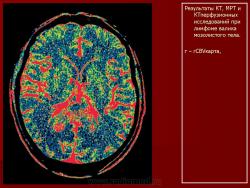

ГМ. Онк. Лимфомы головного мозга. Набор изображений. +

Лимфомы головного мозга.